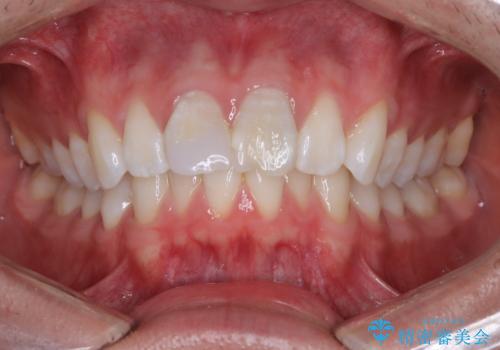

【ワイヤー矯正 11ヵ月で矯正終了!】歯のでこぼこを治したい!

- 「歯のでこぼこを治したい 1年くらいで矯正を終わらせたい」を主訴に来院された患者様です。

叢生量は多く無く歯の傾斜も標準傾斜だったので歯は抜かずにワイヤー矯正で治療を行いました。

左側は2級傾向が強く臼歯の遠心移動をご提案しましたが、1年以内に矯正を終わらせたいという患者様のご意向で希望されず叢生を改善する矯正となりました。